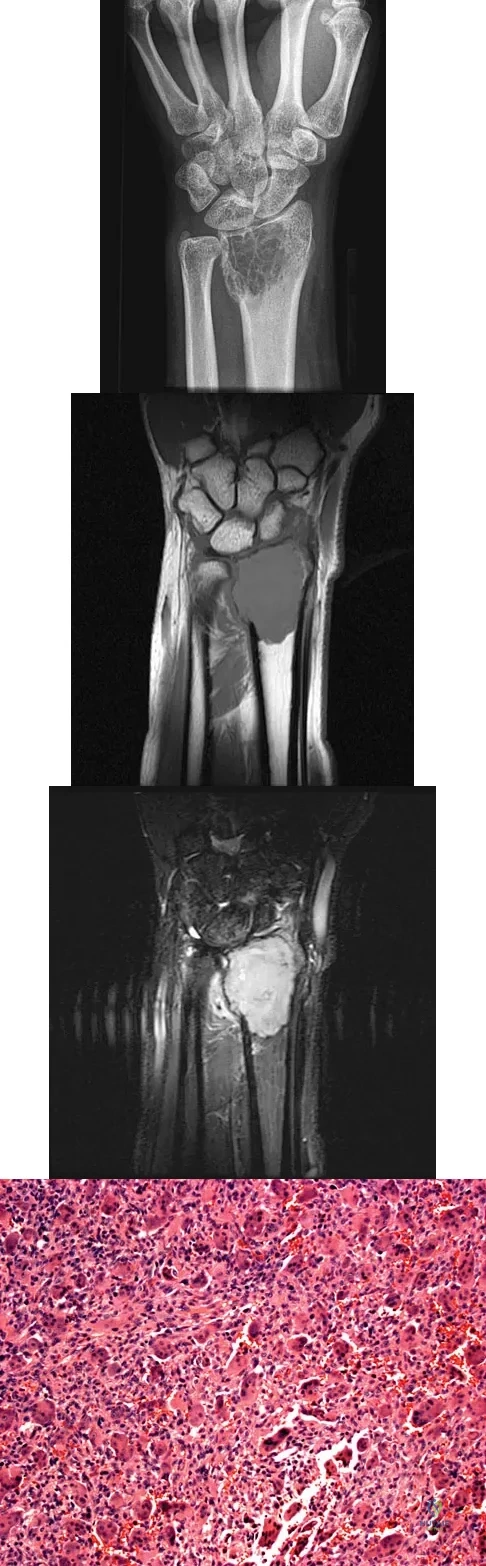

A 20-year-old woman has had wrist pain for the past 5 months. A radiograph, MRI scans, and biopsy specimen are shown in Figures 46a through 46d. The patient is then treated with intralesional surgery. The patient should be counseled that her risk of developing lung metastasis is approximately what percent?

Explanation